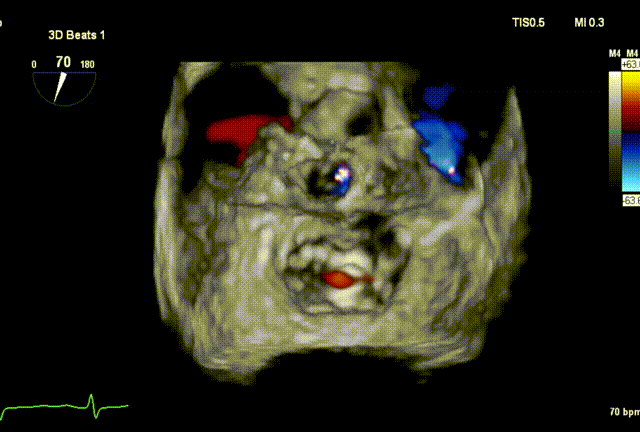

术前3D

DMR P2脱垂连枷(脱垂范围:12mm,连枷间距:3mm),反流2区,MR重度(VC:4* 10mm),A2:21mm,P2:10mm,AP:30mm,MVA约 4.7 cm²。